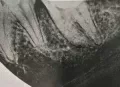

Около 3-х лет назад мне удалили нервы из верхней правой шестерки. Спустя 2 года воспалились корни, т.е. около 9 месяцев назад перелечивали корни, поставили коронку. Месяц назад зуб снова заболел, оказалось воспаление под корнем.

Хотелось бы узнать, действительно ли есть воспаление? И вообще в целом ситуацию насчет этого зуба, какое лечение следует предпринять? Есть 2 панорамных снимка.

Действительно, в зубе имеется хронический воспалительный процесс, причина — некачественное лечение каналов. Зуб будет лечиться в несколько посещений, и при квалифицированном подходе его вполне можно спасти.